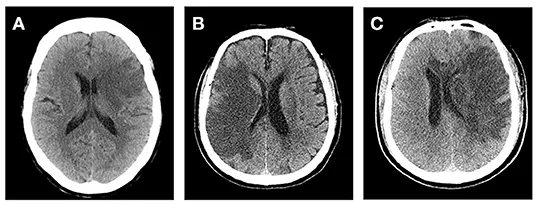

Hemorrhagic Transformation

- Ischemic tissue converts into a hemorrhage.

- Major risk factors: Large infarct size, thrombolysis (tPA), anticoagulation.

- Action: Immediately stop offending agents; urgent neurosurgical evaluation.

⭐ Malignant MCA Syndrome: A devastating complication in large MCA strokes with massive edema. Decompressive hemicraniectomy within 48 hours of stroke onset is life-saving and improves outcomes in patients <60 years.

- Cerebral edema is a peak cause of mortality 3-5 days post-stroke; manage with hyperosmolar therapy (mannitol, hypertonic saline).

- Suspect hemorrhagic transformation with neurologic worsening after tPA; get an immediate non-contrast CT.